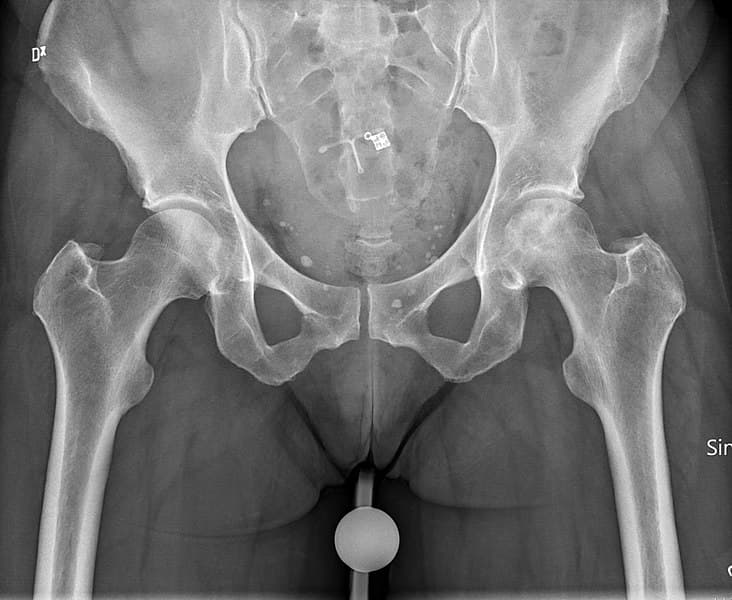

Avascular necrosis is a degenerative bone condition. It is a disease that is a result of the short term or permanent loss of blood supply to the bone. The lack of blood supply to the bone can lead to tiny breaks in the bone which can cause the bone to collapse. The condition is also known as osteonecrosis. If avascular necrosis occurs near a joint, the joint surface may in turn collapse. The most common sites of avascular necrosis are the femoral head, knee, talus, and humeral head. The hip is the most common site of avascular necrosis.